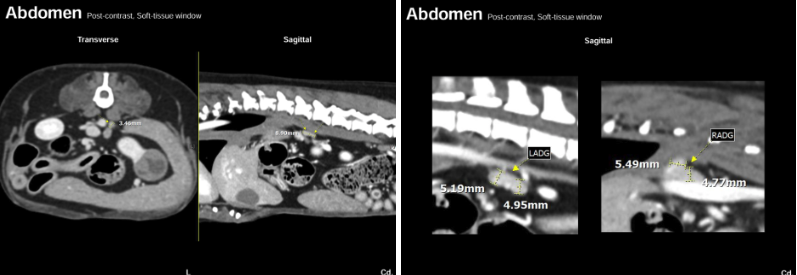

강아지 신장암 CT영상 : 종양성 변화를 보이는 좌측 신장

강아지 신장암 CT영상: 비대된 림프절과 정상크기의 부신